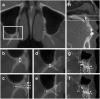

Maxillary osteotomy is a common surgical procedure and often involves separation of the pterygomaxillary junction (PMJ), which is a "blinded" procedure with inherent risks. Knowledge of the PMJ structure is essential. It remains unclear whether patients with different facial types have different PMJ structures, or different surgical outcome. This study evaluated the computed tomographic images of 283 consecutive patients who received orthognathic surgery. Patients were classified into Angle class I, II, III and cleft lip/palate groups. The results showed that the PMJ was 5.1 ± 1.4 mm in thickness, 9.7 ± 1.7 mm in width, and 102.0 ± 4.0 degrees relative to the sagittal plane in the level of posterior nasal spine. There were no statistically significant differences in these measurements among the groups. The class III group demonstrated significantly smaller angle relative to the maxillary occlusal plane. The cleft group showed significantly longer vertical distance between the posterior nasal spine and the lower border of PMJ, shorter distance between the second molar and PMJ, and longer distance between the descending palatine artery and PMJ. With regard to postoperative outcome, the cleft group showed higher incidence of pterygoid plate fracture. The results in this study provide additional surgical anatomic information.